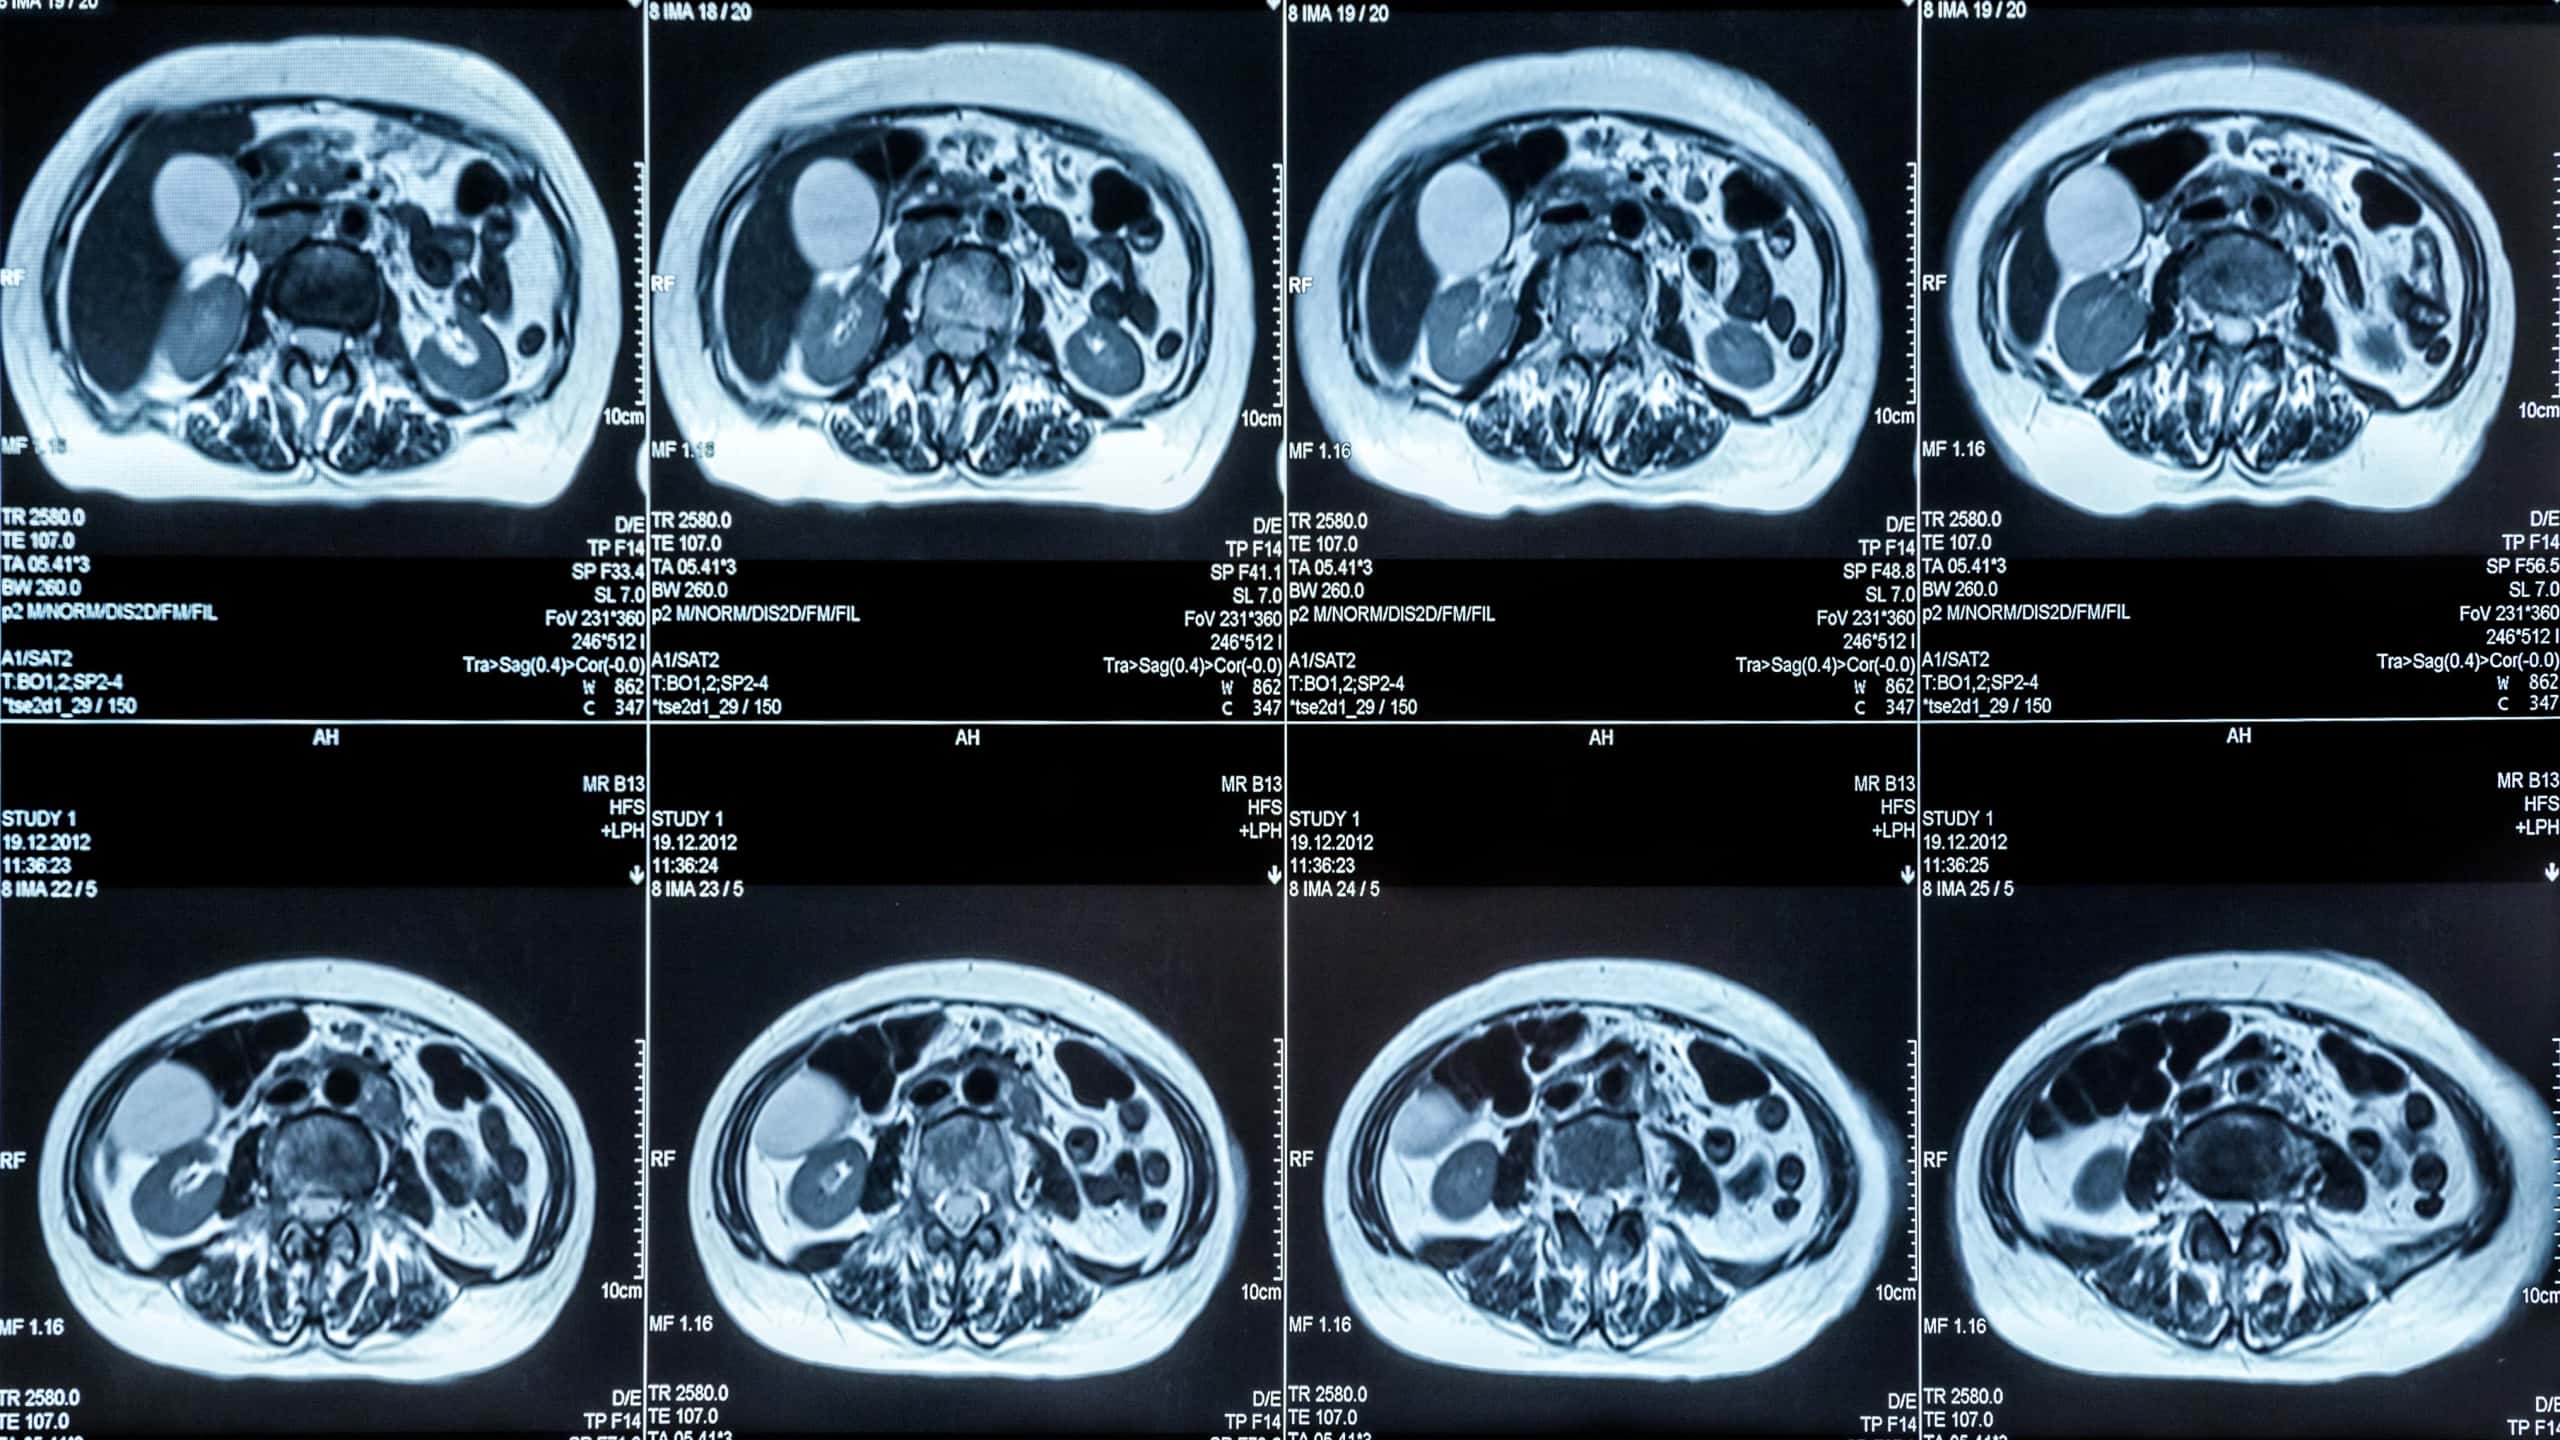

MRI와 MRA, CT, 초음파, PET-CT 등 대부분의 정밀 영상검사는 급여·비급여 여부와 관계없이 치료 목적이고 실제 본인부담금이 발생했다면 실손 청구 대상이 된다. 다만 최근 실손보험은 비급여 항목을 세대별로 분리 관리하는 구조로 바뀌었기 때문에, 특히 고가의 비급여 MRI는 세대별 차이가 크게 나타난다.

입원 치료 중 시행된 MRI나 CT, 초음파 검사는 실손보험에서 입원의료비 보장 항목으로 분류되어 보장된다. 수술비, 약제비, 검사비가 하나의 입원 진료비로 합산돼 청구되며, 약관에 따른 자기부담금을 공제한 뒤 입원의료비 한도 내에서 실손보험금이 지급되는 구조다. 이 때문에 검사 비용이 높더라도 입원 상태라면 통원보다 보장 한도가 넉넉해 체감 보장액이 크게 느껴지는 경우가 많다.

반면 통원으로 시행한 정밀 영상검사는 입원의료비가 아닌 통원의료비 담보로 처리된다. 이 경우 실손보험 세대별 구조 차이가 그대로 드러난다. 특히 1·2세대 실손은 통원 1일 한도 제한이 있어, MRI처럼 비용이 큰 검사는 상당 부분이 본인 부담으로 남는 사례가 적지 않다. 따라서 통원 진료에서 정밀 영상검사를 예정하고 있다면, 자신의 실손보험 세대와 통원 한도를 미리 확인해 비용 부담을 예측하는 것이 중요하다.